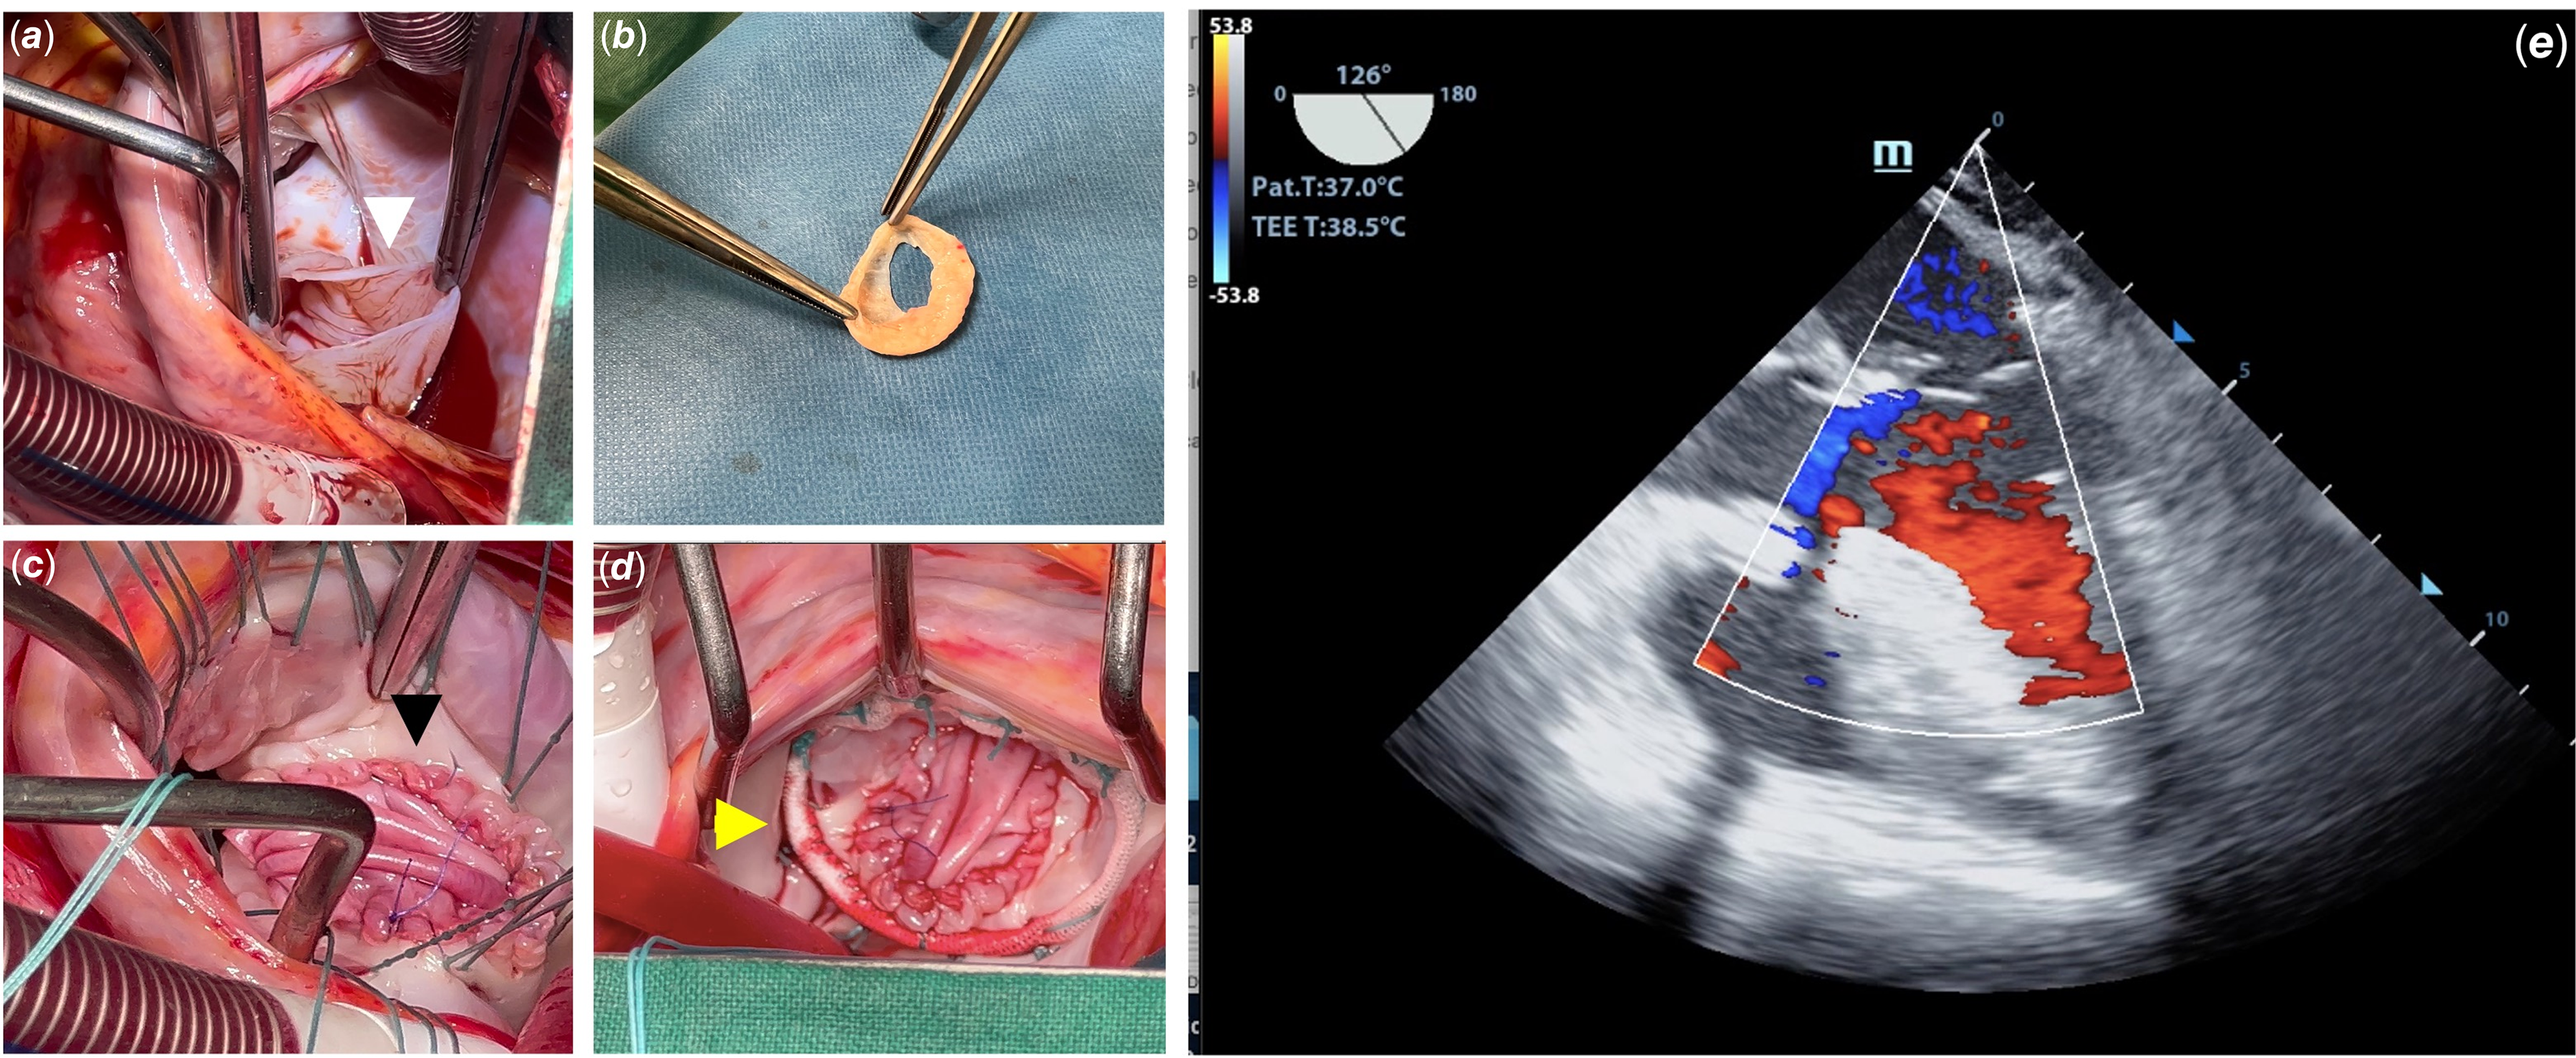

A 26-year-old black woman presented with a 1-year history of progressive dyspnoea. Physical examination revealed a grade 3/6 systolic murmur in the mitral valve area. The physical examination and laboratory test results were unremarkable. Chest radiography revealed cardiomegaly with a cardiothoracic index of 0.63. Electrocardiography showed a sinus rhythm with a heart rate of 69 beats/min and signs of left atrial dilatation with no other alterations. A transthoracic two-dimensional echocardiogram revealed a saccular formation arising from the posterior leaflet of the mitral valve (Fig 1A). The aneurysm ruptured into the left atrium (Fig 1B), generating regurgitation in Doppler colour (Figs 1C and 1D). The patient underwent open-heart mitral valve surgery by transatrial approach, and after left atriotomy, a saccular aneurysm ruptured into the left atrium, as demonstrated by echocardiography (Fig 2A). The aneurysm was removed (Fig 2B). An aneurysmal form was observed in the region where the posterior annulus was destroyed; it was closed with a bovine pericardium and a separated suture. Subsequently, the posterior annulus and the leaflet were reconstructed with autologous pericardium fixed in glutaraldehyde solution (Fig 2C). A flexible artificial ring (No. 32; Medtronic Inc., Minneapolis, MN, United States of America) was also implanted (Fig 2D). A saline test was performed, and the results were satisfactory. The cardiopulmonary bypass time was 62 min, and the x-clamping time was 57 min. Intraoperative echocardiography revealed no aneurysms or regurgitations (Fig 2E). Post-operative transthoracic echocardiography showed a transvalvular gradient of 2.7 mmHg with satisfactory left ventricular function. The patient remained asymptomatic after 2 months of follow-up.

Figure 2. Surgical findings, approach, and post-operative: a shows the aneurysmal sac ruptured into the left atrium (white arrow). b shows the aneurysmal sac with the exit hole for the left atrium. c demonstrates the aspect after the annulus reconstruction and posterior leaflet enlargement with autologous pericardium (black arrow). d shows the prosthetic ring used to reinforce the ring (yellow arrow). e shows a post-operative transesophageal two-dimensional echocardiogram with no residual aneurysm or mitral valve regurgitation. Ao = aorta; LA = left atrium.